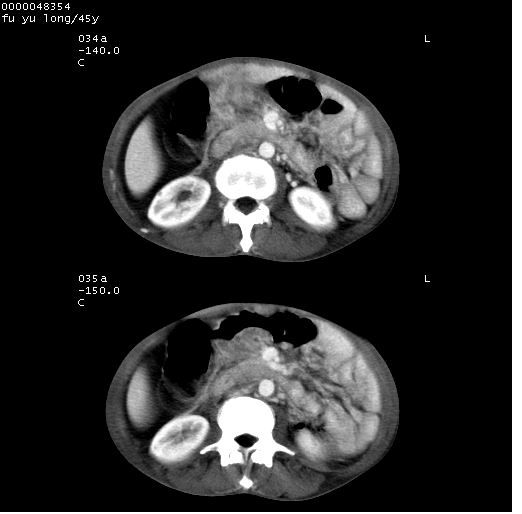

以下是引用医影拾贝在2008-5-30 2:38:00的发言:[br]气肿性胃炎、胃十二指肠溃疡、腹膜炎,考虑穿孔可能性较大

以下是引用lkc8963在2008-5-30 8:44:00的发言:[br]胃窦癌伴网膜(胃结肠韧带)/腹膜及腹膜后淋巴结转移.